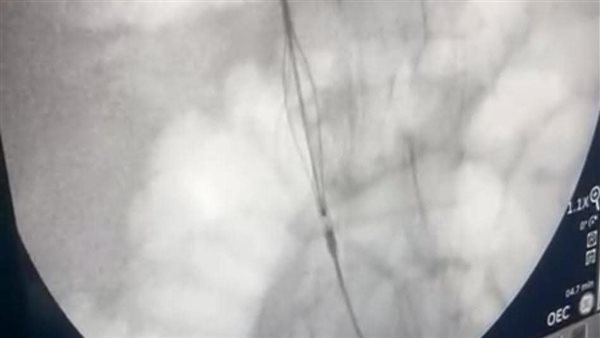

نجاح فريق طبي بقسم جراحة الأوعية الدموية في استحداث خدمة طبية دقيقة ومتقدمة من خلال إجراء تركيب فلتر وريدي بالوريد الأجوف السفلي (IVC Filter) باستخدام القسطرة التداخلية، وذلك للوقاية من حدوث الجلطات الدموية ومنع انتقالها إلى الشريان الرئوي (Pulmonary Embolism)، بما يسهم في إنقاذ حياة المرضى المعرضين لمضاعفات خطيرة.

وأضاف أيضا  أنه تم التعامل مع الحالة وفق أحدث البروتوكولات الطبية، حيث تم استخدام جهاز الأشعة التلفزيونية لعمل مدخل وريدي بالطرف السفلي الأيسر، ثم إجراء تصوير بالصبغة (Cavogram) لتحديد موضع الوريد الكلوي الأيمن (Right Renal Vein)، ومن ثم تركيب الفلتر الوريدي بدقة تحت توجيه القسطرة التداخلية.